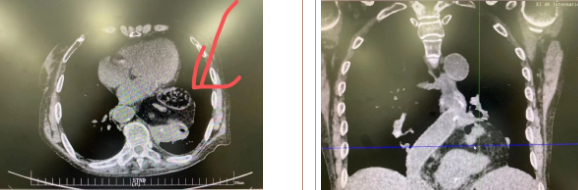

據(jù)了解,患者多年來(lái)進(jìn)食后出現(xiàn)惡心、嘔吐,卻未到醫(yī)院進(jìn)行檢查。3個(gè)月前患者突然出現(xiàn)無(wú)尿,全身腫脹等情況才前往就醫(yī),卻遭多家醫(yī)院拒收,輾轉(zhuǎn)來(lái)到我院就診。檢查發(fā)現(xiàn)患者已患宮頸癌、進(jìn)而引起腎后性腎衰、同時(shí)合并膈疝、出現(xiàn)泌尿道感染,病情及其復(fù)雜。

經(jīng)泌尿外科積極救治,患者腎衰癥狀緩解,隨后轉(zhuǎn)入放射治療中心進(jìn)行宮頸癌根治性放療。放療期間,患者惡心、嘔吐癥狀逐漸加重,后期無(wú)法進(jìn)食,排除機(jī)械性腸梗阻和放療因素,考慮因長(zhǎng)期膈疝加重引起,經(jīng)胸外科會(huì)診后轉(zhuǎn)入胸外科一病區(qū)準(zhǔn)備手術(shù)治療。

麻醉手術(shù)中心副主任丁倩為減輕患者術(shù)后不適,實(shí)施單腔聯(lián)合支氣管封堵插管,同時(shí)進(jìn)行了肋間神經(jīng)阻滯麻醉。術(shù)中發(fā)現(xiàn)患者膈疝巨大,食管和疝囊分界不清,部分胃組織和結(jié)腸疝已進(jìn)入胸腔。李文海憑借豐富的臨床經(jīng)驗(yàn),仔細(xì)辨別解剖變異,有序完成分離、縫合、修補(bǔ)等一系列操作,胸外科穆強(qiáng)副主任醫(yī)師、劉歡住院醫(yī)師、麻醉手術(shù)中心團(tuán)隊(duì)通力配合,手術(shù)最終順利完成,患者安全返回胸外科監(jiān)護(hù)室病房。目前患者術(shù)后恢復(fù)良好,于近日準(zhǔn)備出院。